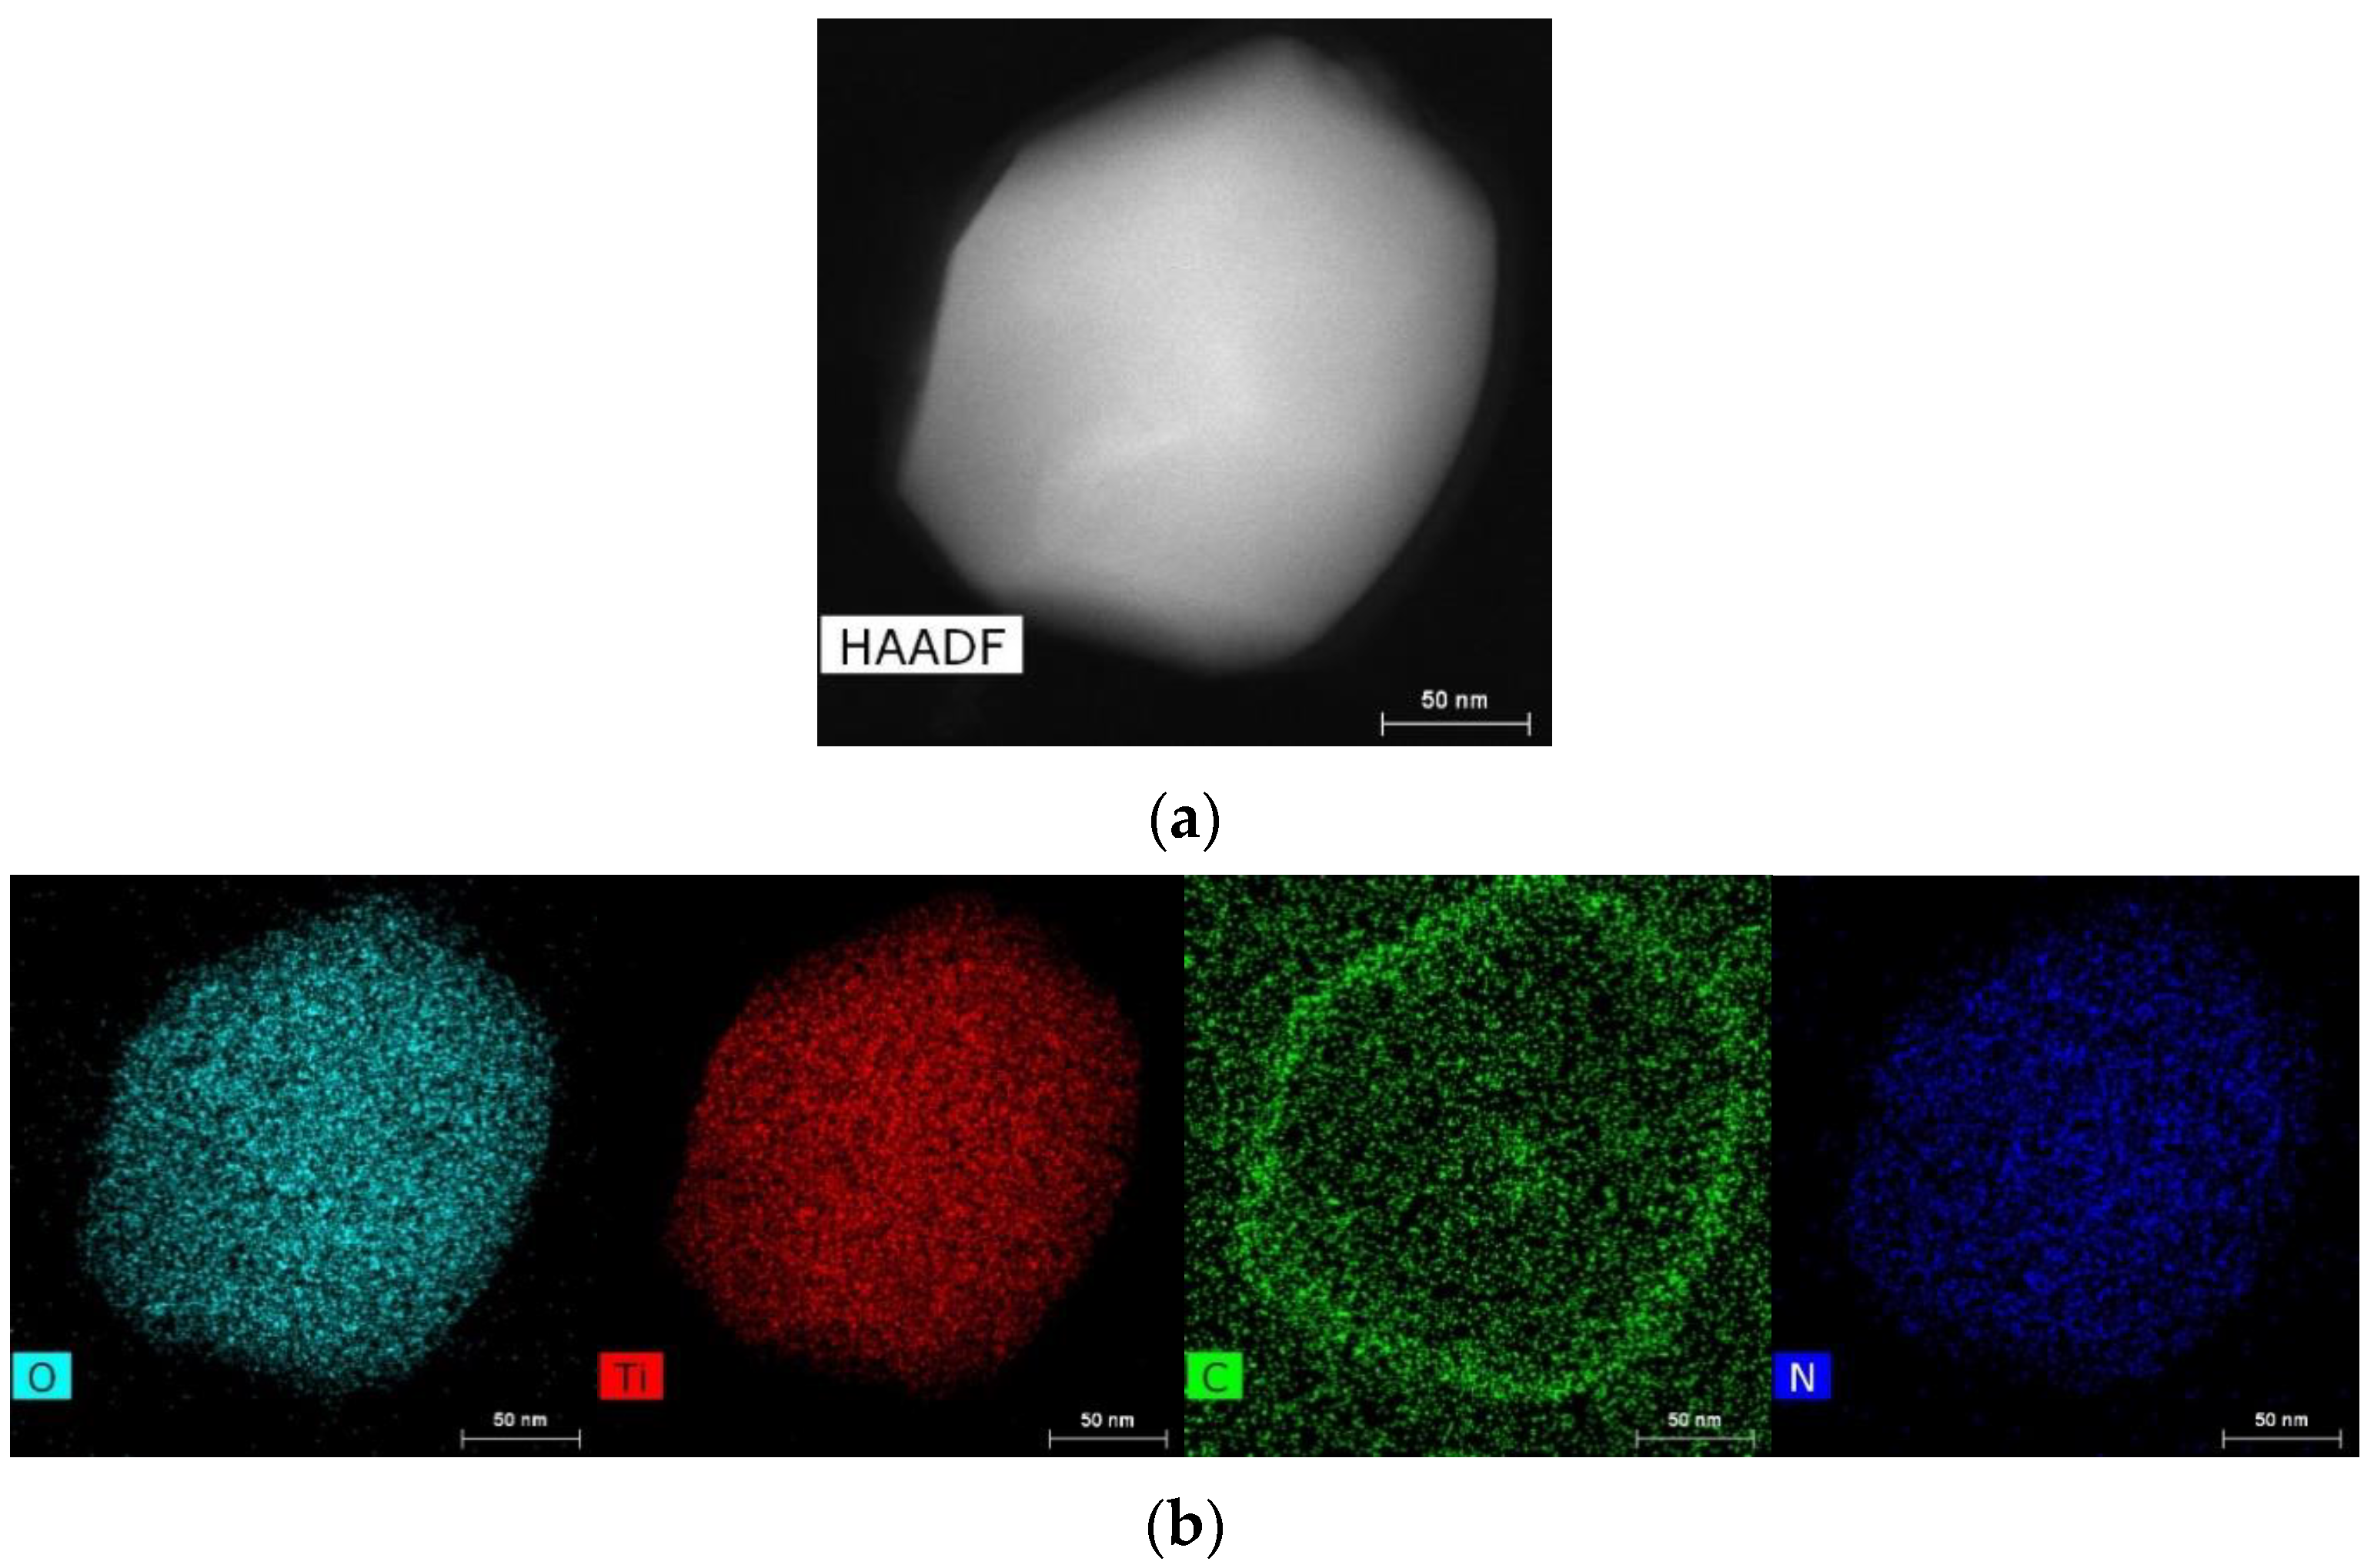

4.4. Methods of Scanning Electron Microscopy (SEM) and Transmission Electron Microscopy (TEM) with Energy Dispersive (ED) Analysis

2.1.1. Results of X-ray and Electron Microscopic Studies